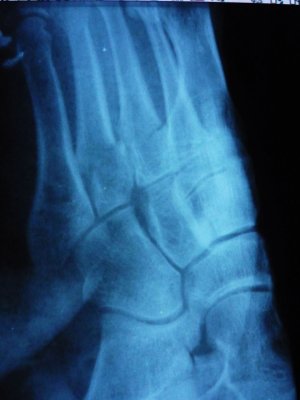

Здравствуйте, 16.10.09 в пятницу вечером на тренировке разворачиваясь на одной ноге сломал 3 и 4 плюсневые кости ,в травмопункте сделали снимки, после чего дежурный врач накладывая гипс попытался вправить смещеные плюсневые кости, но у него ничего не вышло, что видно на повторном снимке .Посоветовал с понедельника обратится в больницу по месту жительства и возможно готовится к операции.... Посмотрите пожалуйста можно ли вправить на место кости без операционного вмешательства и каковы шансы на их успешное ПРАВИЛЬНОЕ сростание.